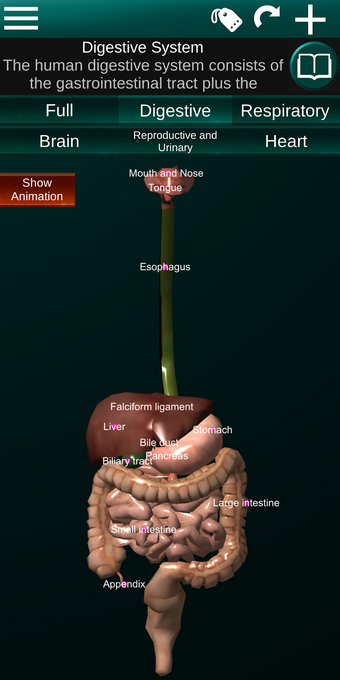

Diese Anwendung zeigt ein dreidimensionales Modell der menschlichen Körperorgane und eine Beschreibung aller von ihnen.

Sie können jedes Organ wie Herz, Gehirn, Lunge, Fortpflanzungssystem, Leber, Darm, Eierstock, Hoden, Magen, Niere usw. anfassen.

Sie ist für alle Menschen nützlich, auch für Studenten, da jedes Anatomieorgan in einer anderen Farbe dargestellt ist.

Sie können die App verwenden, um herauszufinden, welches die verschiedenen Körperorgane sind und welche Funktionen sie haben.